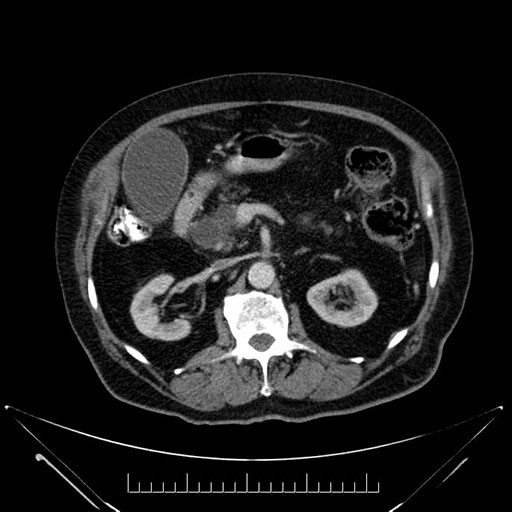

Whipple (pancreaticoduodenectomy) [case 7]

Imaging Analysis

Look through the patient's CT scan to identify any areas of concern for the necessary procedure.

Based on your CT findings, which issue(s) would give reason for "planned slowing down moment(s)" in this case?

Considering a standard Whipple procedure, what step(s) of the operation would you do differently in this case?